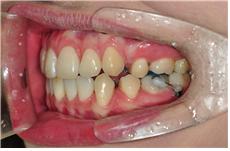

와이어와 고무줄 교체~

별 다른 진행없이 와이어만 교체하는 것은 제 앞니 때문인데요 ~

그래서 이번 월치료에는 하악와이어교체해주시고~ 고무줄들을 새 것들로 교체해주셨어요~